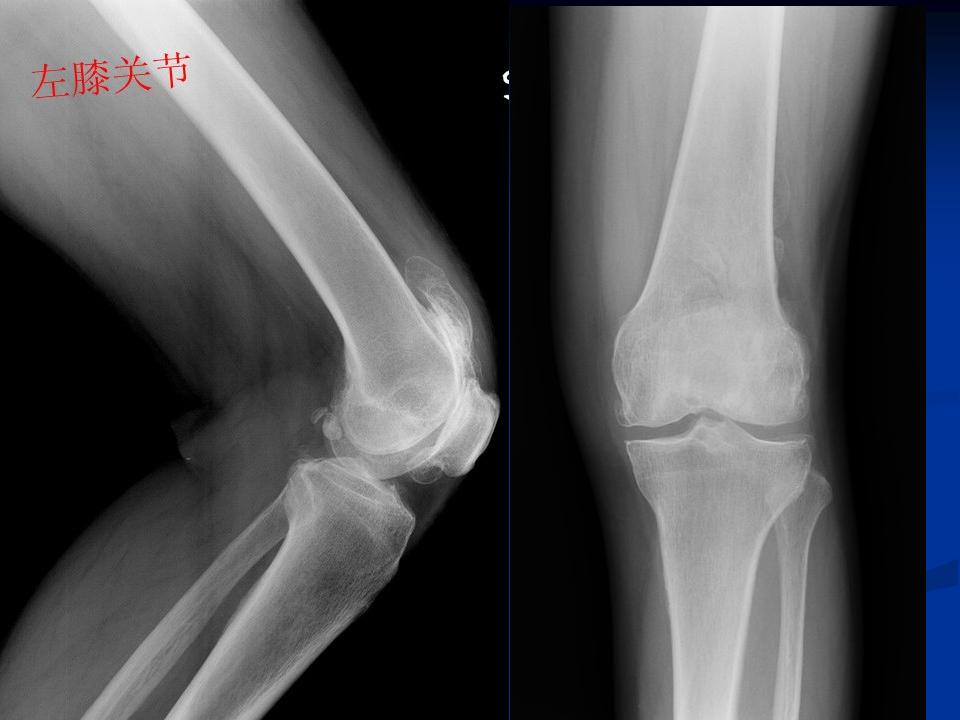

影像学检查 X线 四个方向X线影像 l 早期可无改变 l关节间隙变窄、不均匀、消失(成人<3mm; 老年人<2mm)。 l骨赘形成 l关节内游离体、骨质疏松 l软骨下骨板硬化、囊性变

膝关节退行性变(胫骨平台软骨下钙化)